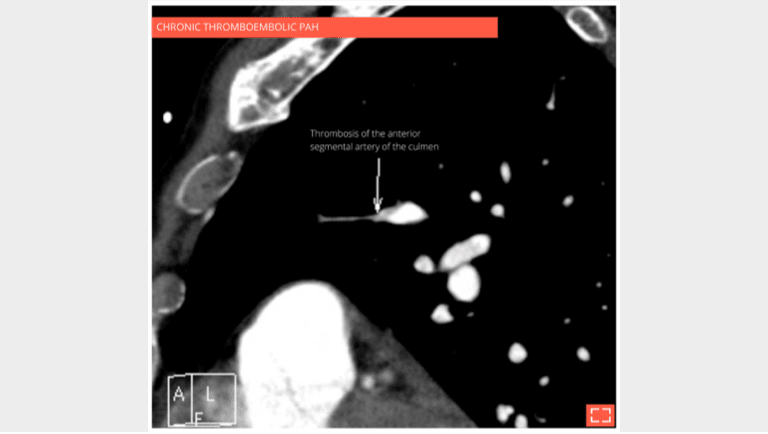

The CT scan with contrast medium injection to check for pulmonary artery obstruction shows the small size and distal thrombosis of peripheral pulmonary arteries, confirming chronic thrombosis. Ventilation-perfusion scintigraphy is the recommended exam for screening for these anomalies.

3. Vascular mosaic attenuation

Vascular mosaic attenuation